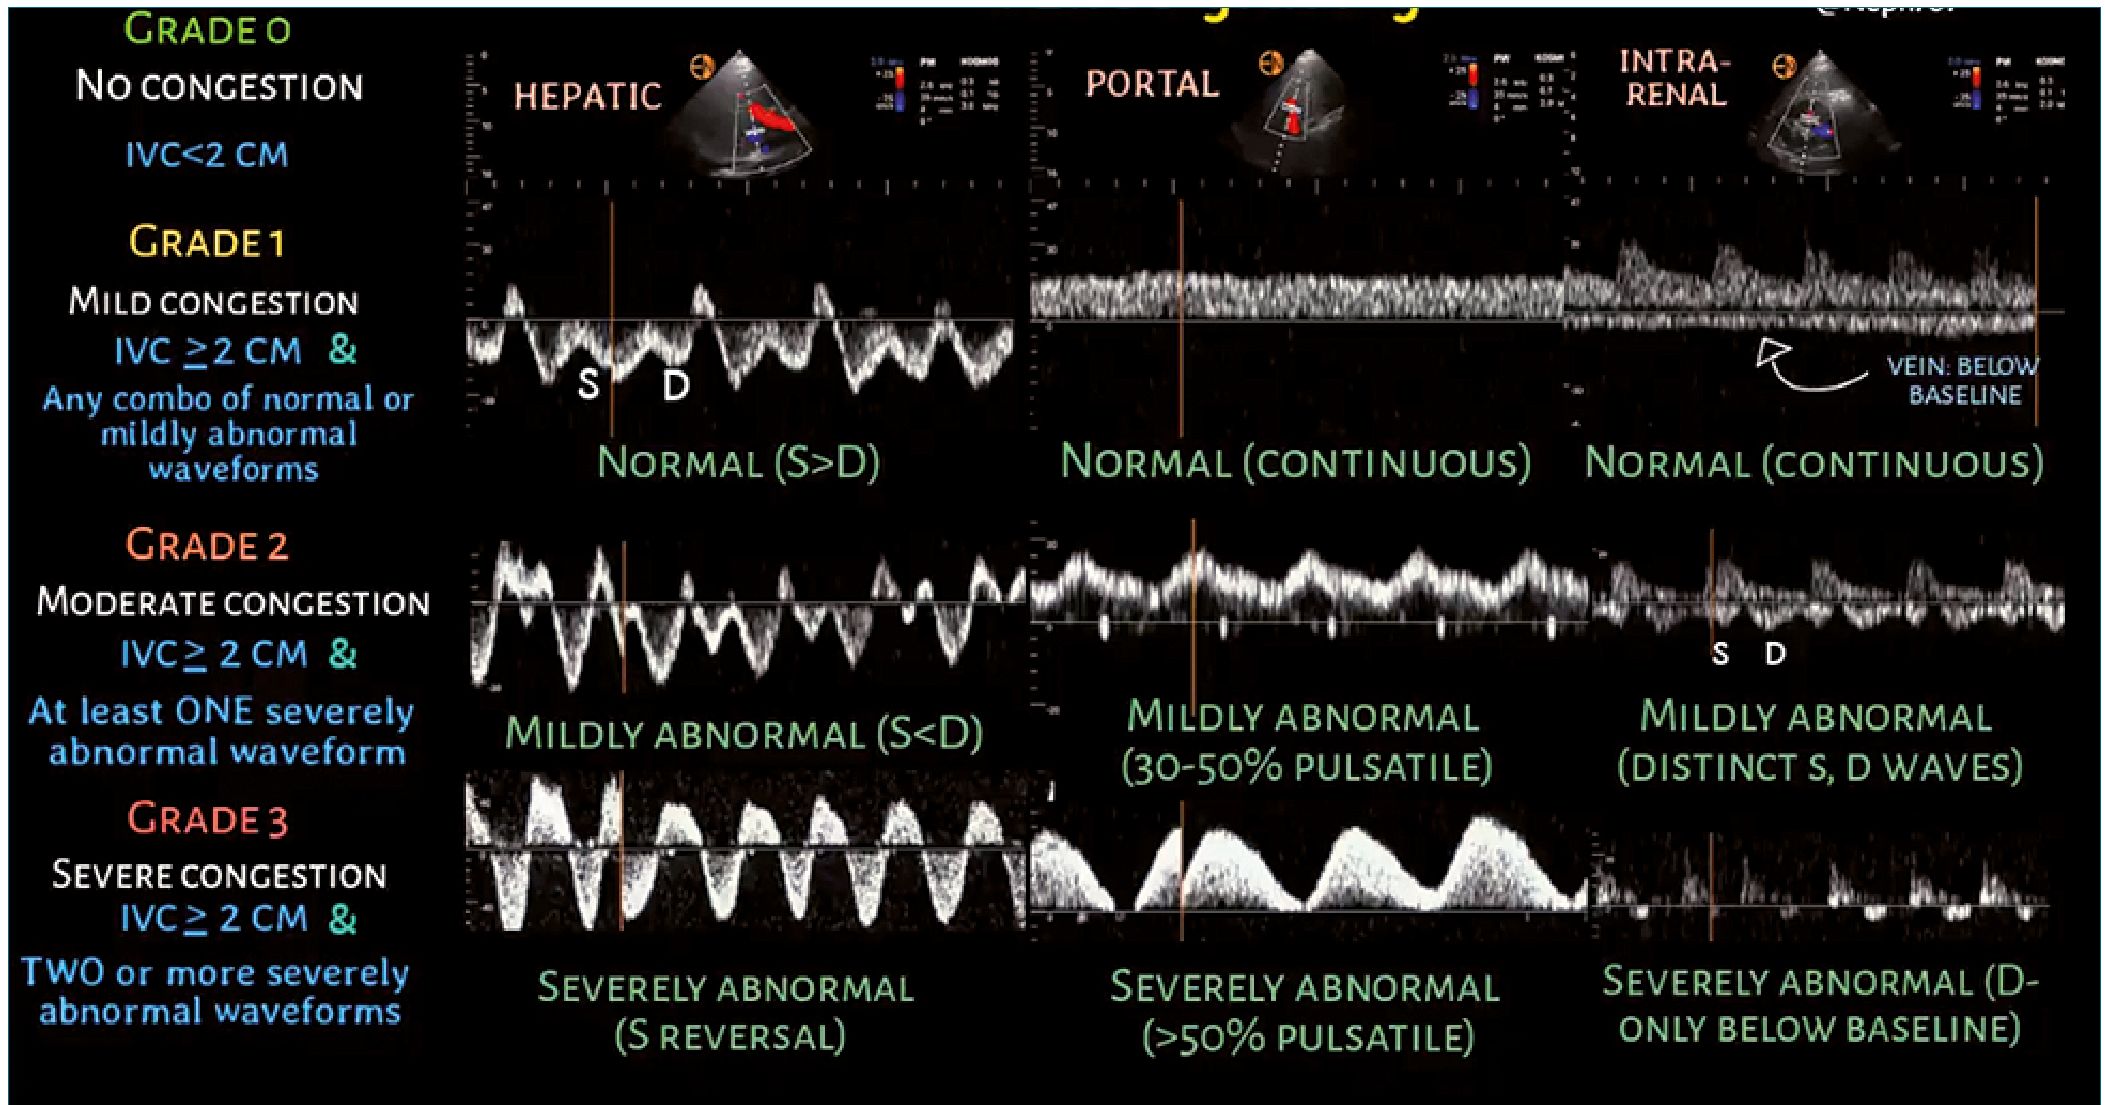

El análisis Doppler de la vena porta, la vena hepática y la vena venosa intrarrenal se utiliza en el sistema de clasificación VExUS. En presencia de una vena cava inferior sin colapso, cada una de estas venas se evalúa y se asigna a congestión normal, leve o grave[2] (Figura 1).

Figura 1. Sistema de puntuación VExUS para la determinación ecográfica de la congestión venosa. Tomado de Koratala A. VExUS flash cards [Internet]. NephroPOCUS. 2021 [citado 17 de febrero de 2023]. Disponible en: https://nephropocus.com/2021/10/05/vexus-flash-cards/. Con permiso del autor.